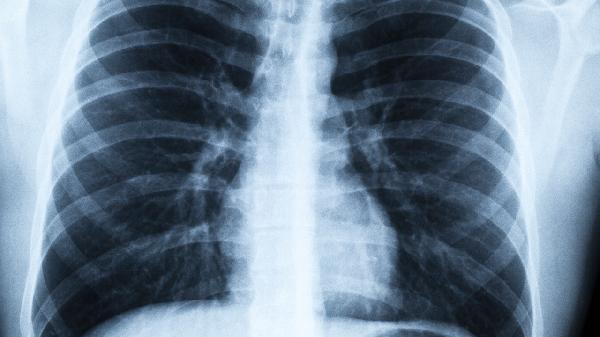

建议到呼吸科或肿瘤专科就诊,低剂量螺旋CT是目前最有效的筛查手段。